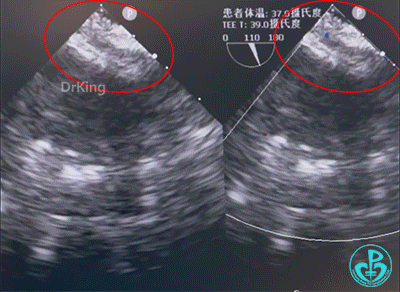

钢缆和鞘管轻轻抵住房间隔,固定钢缆和鞘管并牵拉成型线锁定,超声下观察封堵器形态,封堵器呈工字形稳定骑跨于房间隔两侧,成型良好。

牵拉试验时,封堵器形态稳定,形态未发生改变,判定锁定成功。

最后封堵器盘面稳定夹持房间隔,封堵器成型良好,未见分流,封堵成功。